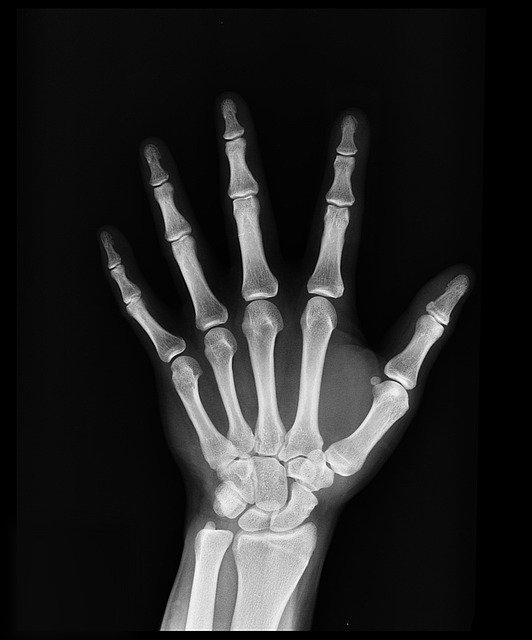

X-ray로 성장판을 검사하면 손이나 골반, 무릎관절, 팔꿈치관절, 발목관절을 사용해서 골연령을 평가하는데요.

신체의 여러 뼈 중에 왼쪽 손목을 X-ray 촬영하는 것이 가장 정확한 검사 방법입니다.

손목뼈는 뼈조직이 만들어지는 순서가 일정하고 다른 부위의 사진과 비교해도 정확도가 떨어지지 않는데다가 촬영이 용이하기 때문이죠.